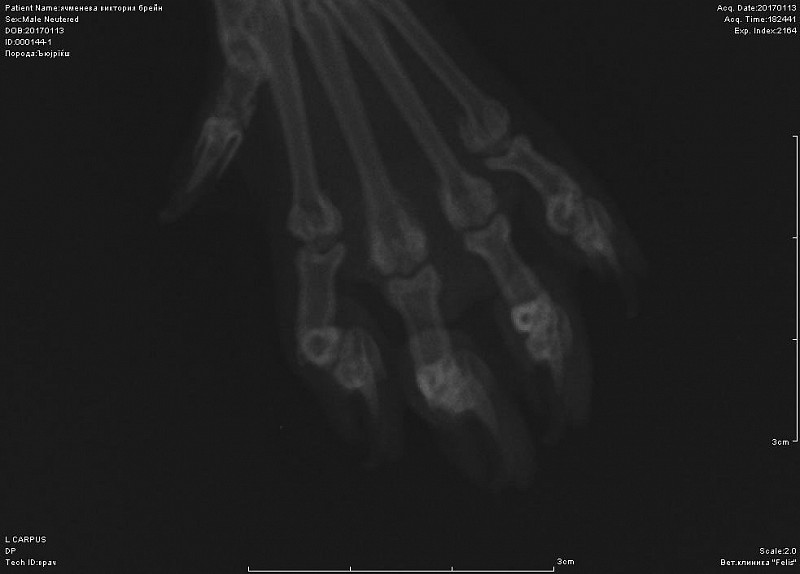

Добрый день! не вижу перелома на этом снимке. Нужна еще прямая проекция. Боль именно в запястном суставе?

Вот снимок, посмотрите, пожалуйста.

Спасибо за ответ, вот увеличила все.

еще

вот в запястном суставе не вижу изменений.А вот локтевом есть признаки артроза. Но все же это не прямая и даже не боковая проекция локтя.